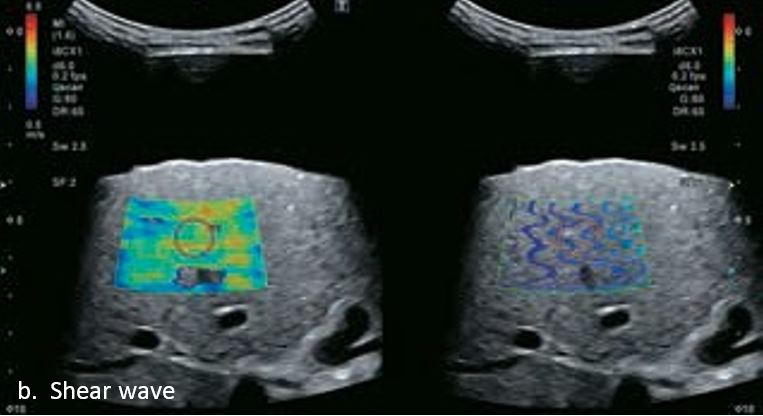

LI-RADS 4 множинні ГЦК

Це випадок 60-річної жінки з декомпенсованим цирозом печінки з асцитом. На сірошкальному зображенні можна виявити два вогнищевих ураження, розміром 21 мм і 10 мм відповідно, розташовані в сегменті 5. Оскільки дослідження методом зсувної хвилі на апараті Canon виконується штовхаючим імпульсом, пацієнтам з асцитом не можна проводити дослідження за допомогою зсувної хвилі, для визначення стадії фіброзу. На ранній артеріальній стадії гомогенне гіперехогенне підсилення спостерігається в обох ураженнях. Ураження є ізоехогенними в портальній венозній та пізній фазах, вимивання не спостерігається через 6 хвилин після ін'єкції, тому ці ураження були класифіковані як LI-RADS 4, ймовірна ГЦК. Важливо знати, що LI-RADS 5 - це ГЦК зі 100% вірогідністю, і вона не потребує біопсії. Значна кількість LI-RADS M (ймовірно або точно злоякісні, але не специфічні для ГЦК) і LI-RADS 4 (ймовірна ГЦК) насправді являються ГЦК.

Малюнок 11